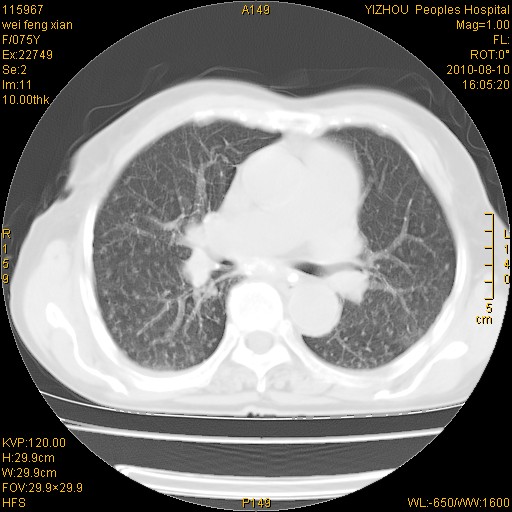

标题: CT28313:两肺弥漫性病变 [打印本页]

标题: CT28313:两肺弥漫性病变

女,75岁,患者反复头昏乏力面色苍白3年,再发10天入院。临床贫血查因。

双肺间质增生并右肺上叶炎性改变,不除外右肺上叶结核病肺内播散

考虑尘肺并结核;右上肺支气管扩张!

结核、尘肺、支气管肺泡癌都不能除外

右肺上叶继发性肺结核伴肺内血型播散!

考虑右肺上叶继发性肺结核伴两肺播散。